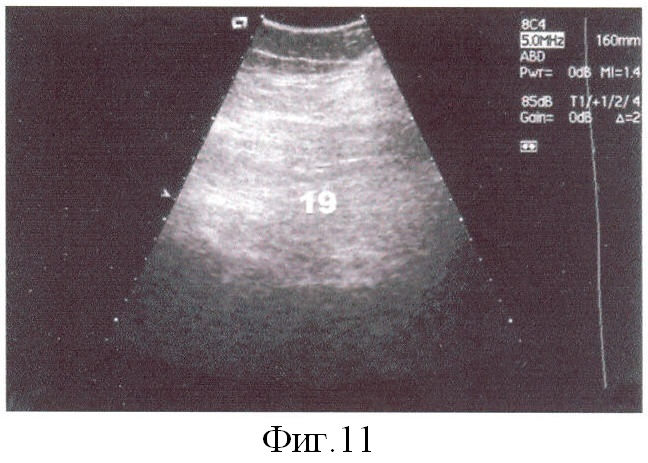

В раннем и отдаленном периодах для контроля за состоянием каналов выполнена эхоабдоминография, показавшая полную облитерацию канальных полостей (фиг.10, поз.18, фиг.11 поз.19). Брюшная стенка при этом была гладкой, без видимых деформаций. Периметр живота в средней трети на протяжении наблюдаемого период оставался в пределах 100±5 см (при исходном размере в 120 см). Вес больной не уменьшился (95 кг при росте 170 см). Рекомендовано соблюдение диеты с целью нормализации ИМТ.